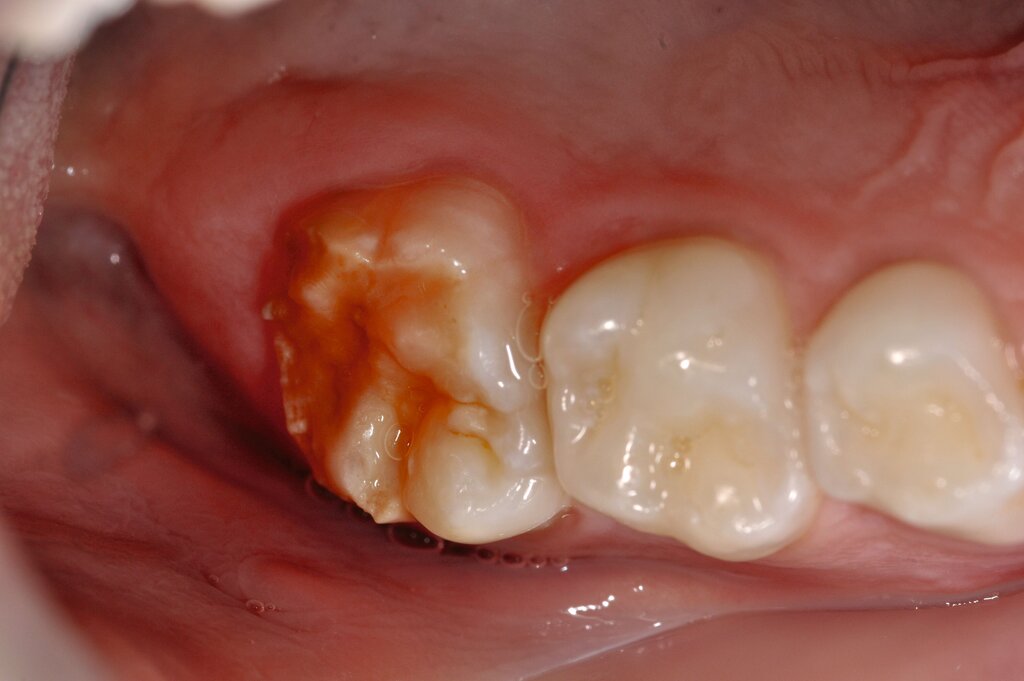

Der Vorteil der Methode ist, dass die betroffenen Zähne auch ohne Lokalanästhesie und Präparation versorgt werden können. Die temporäre Versorgung ermöglicht es, die Patienten an die zahnärztliche Behandlung zu gewöhnen. Häufig führt diese temporäre Versorgung auch zu einer Reduktion der Hypersensitivität der MIH-Zähne. Nachteil der GIZ-Versorgung ist das Risiko einer Füllungsfraktur oder eines vollständigen Verlusts der Füllung (Abbildung 4). Aktuelle Erhebungen bestätigen eine Erfolgsrate von über 80 Prozent nach einem bis zwei Jahren [Durmus et al., 2021; Mahfouz et al., 2025].

Der Behandlungsfall (Abbildung 4d) veranschaulicht die Schwächen des Verfahrens. Wird das Angebot der regelmäßigen Kontrollen nicht wahrgenommen, so droht bei Verlust der Füllung die Kariesprogression. In dem vorliegenden Fall konnte jedoch eine endodontische Maßnahme vermieden und durch die selektive Kariesentfernung die Zahnhartsubstanz weitestgehend erhalten werden.